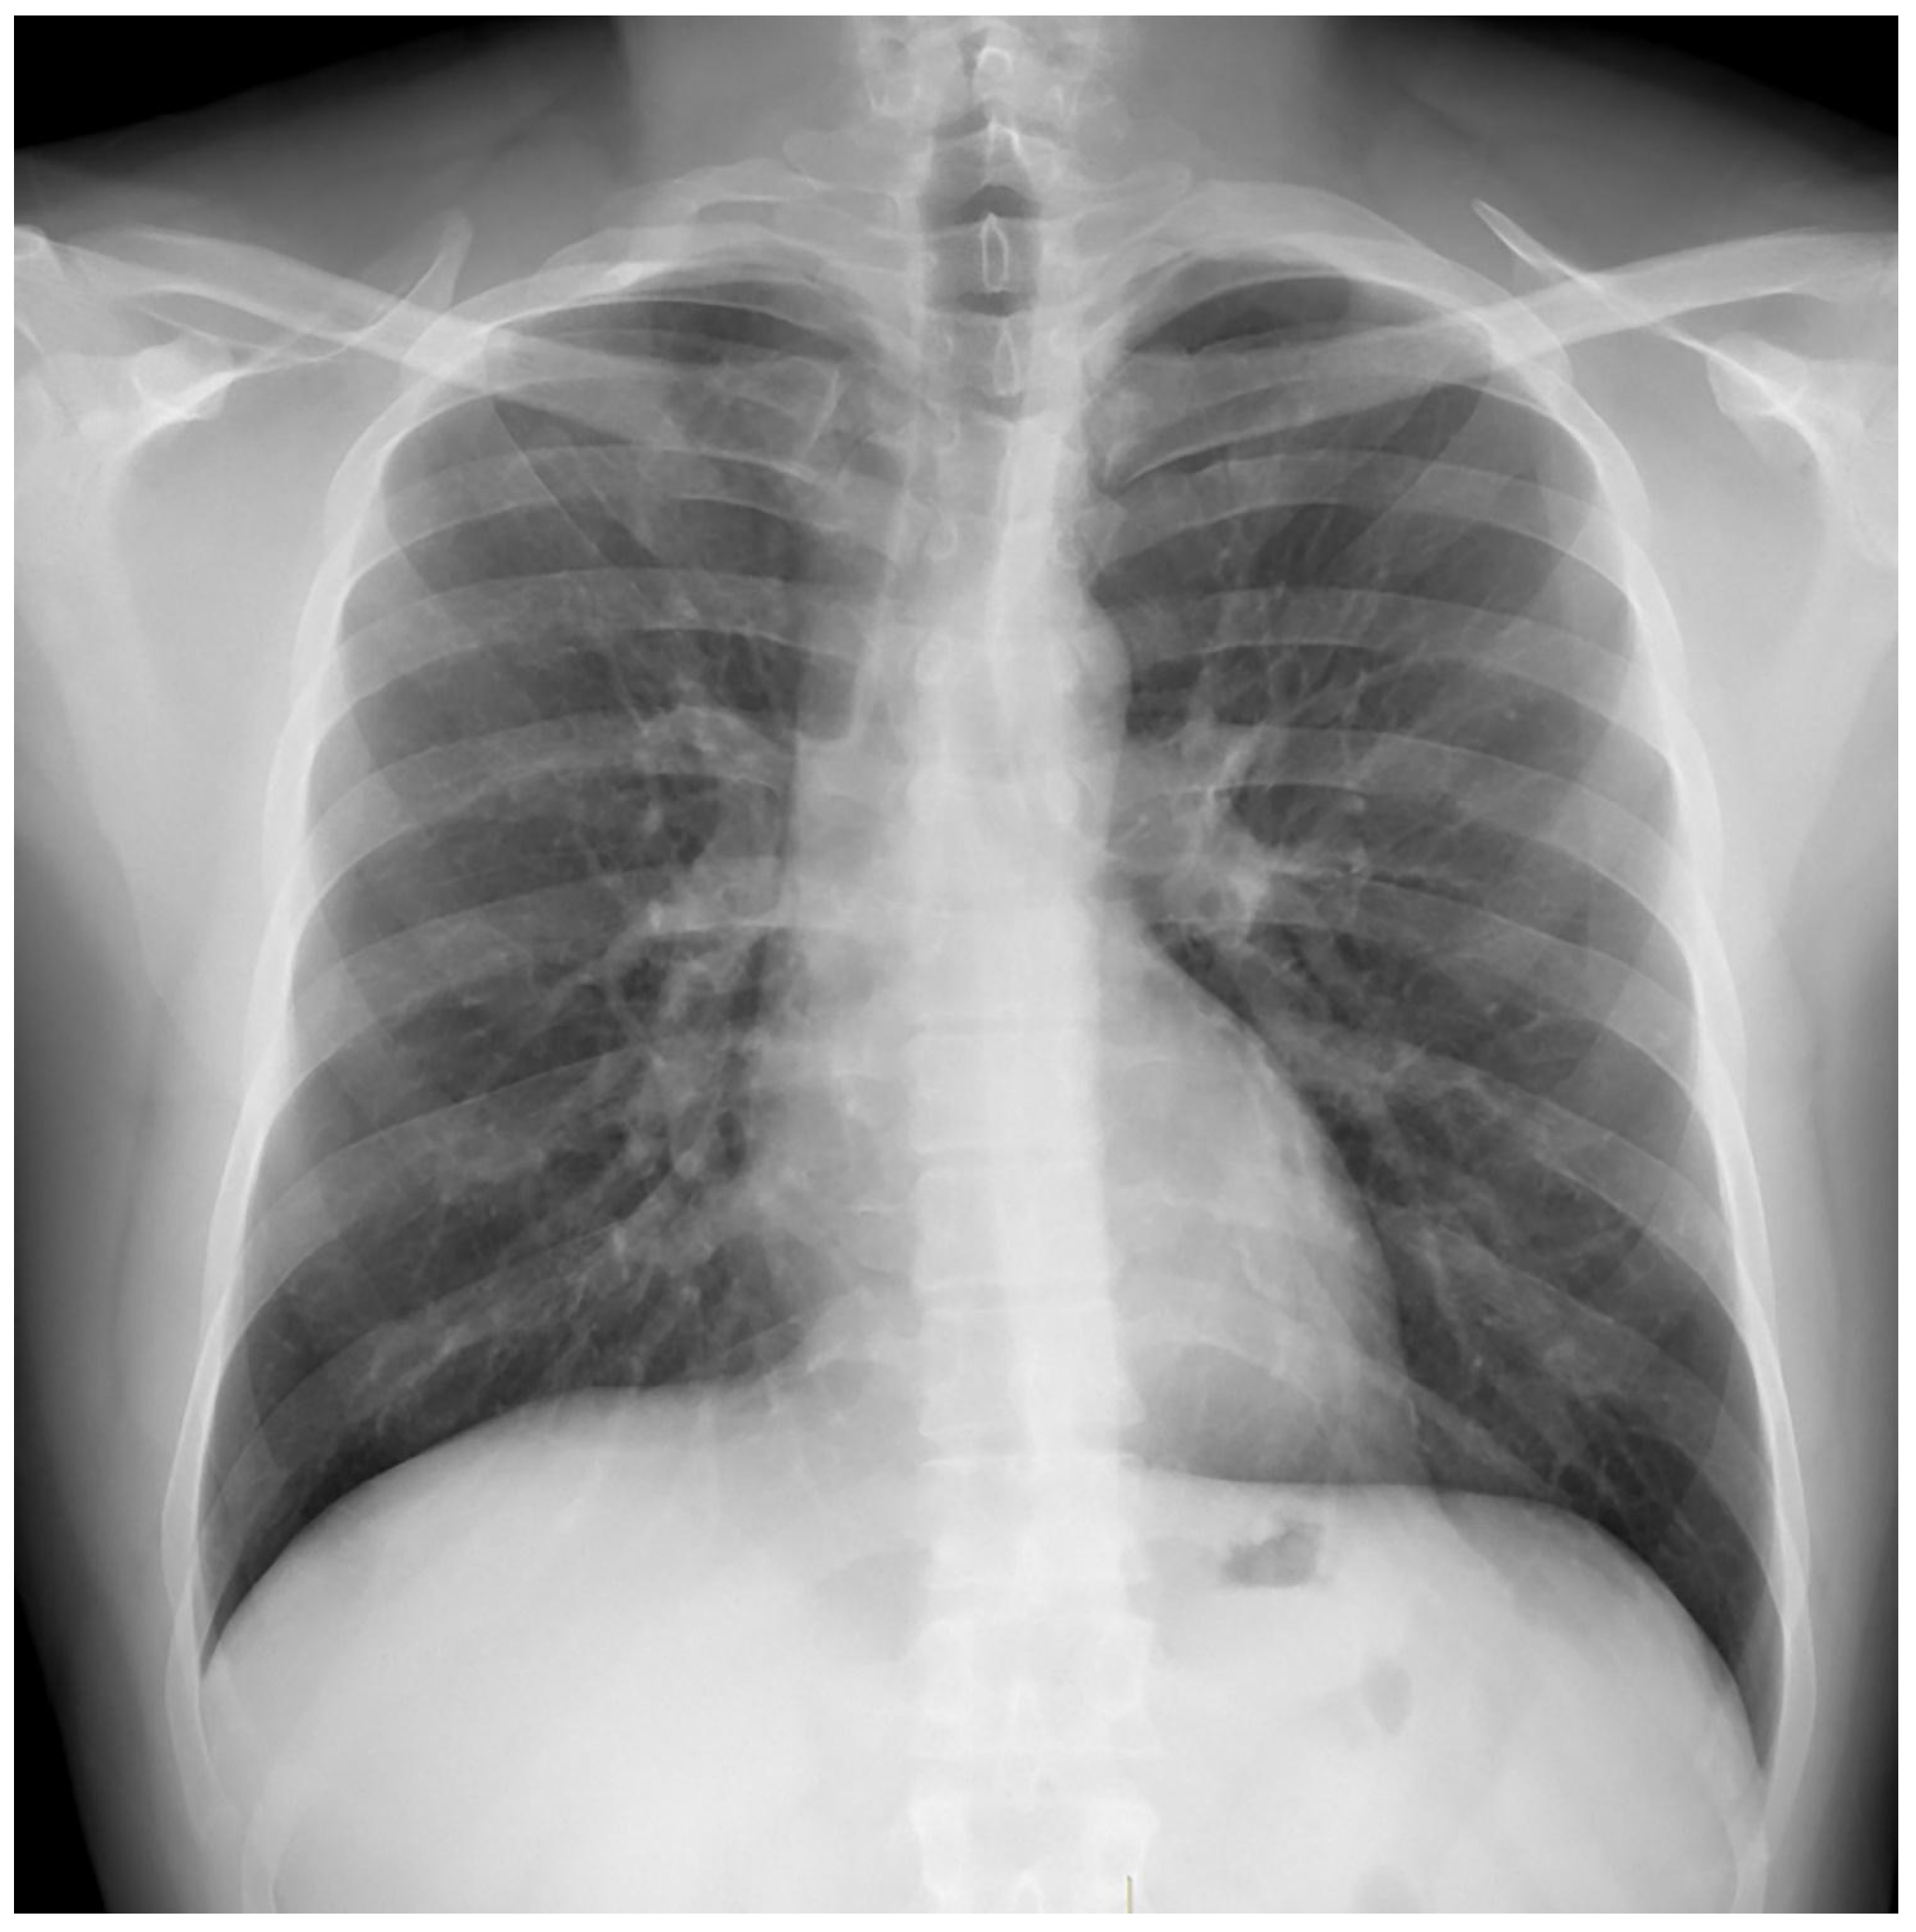

Treatment results of seven patients were reported as follows; two patients as not evaluated (returned to their home country), two patients as completion of treatment, and three patients as cured. The duration of treatments was planned as nine months, and the treatment of the patient with FQ and Z resistance (case 7) continued for 12 months. No recurrence was detected in the first-year follow-up of the five patients who could be followed. Regarding Case 4’s chest X-ray images at the beginning and the 59th day of the treatment (Figure 1 and Figure 2) and Case 7’s chest X-ray images at the beginning and the 12th month of the treatment (Figure 3 and Figure 4) a significant radiological improvement was observed.

Figure 3. Case 7, beginning of the treatment.